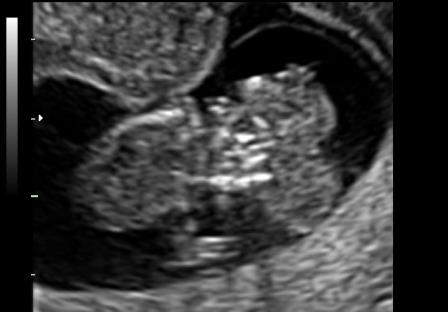

Dopo la 12a settimana per il diretto contatto col liquido amniotico ed i traumi determinati dal contatto con la parete uterina l'encefalo si trasforma in una massa di tessuto molle aderente alla base del cranio determinandosi il quadro dell'anencefalia caratterizzato dall'assenza della volta cranica e da tessuto cerebrale scarsamente rappresentato.

In sezione coronale, per la presenza di macroftalmia, l'estremo cefalico assume il tipico aspetto "a rana".